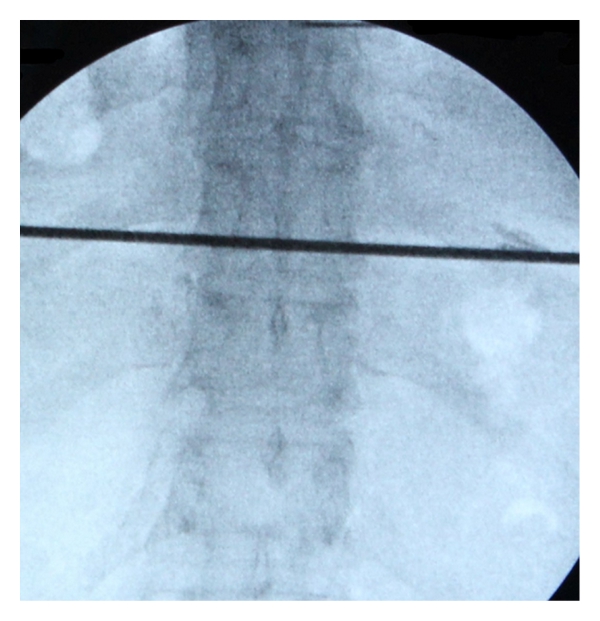

The procedures were performed under local anesthesia with the patient in a prone position on a radiolucent table. The target disc was identified under fluoroscopic guidance (Figure 1(a)), and the entry point between the rib head and the facet (on oblique view) was marked on the skin (Figure 1(b)). Discography was performed to confirm the target disc and to help identify the location of the herniation. The 18 G needle inserted to perform discography was parallel to the upper endplate of the lower vertebral body (Figure 2). The tip of the needle reached posterior disc margin (on the lateral view) and was situated between midline and medial pedicle line (on the AP view). The surgical region was anesthetized with a combination of 0.5% lidocaine and epinephrine.

(a)

(b)